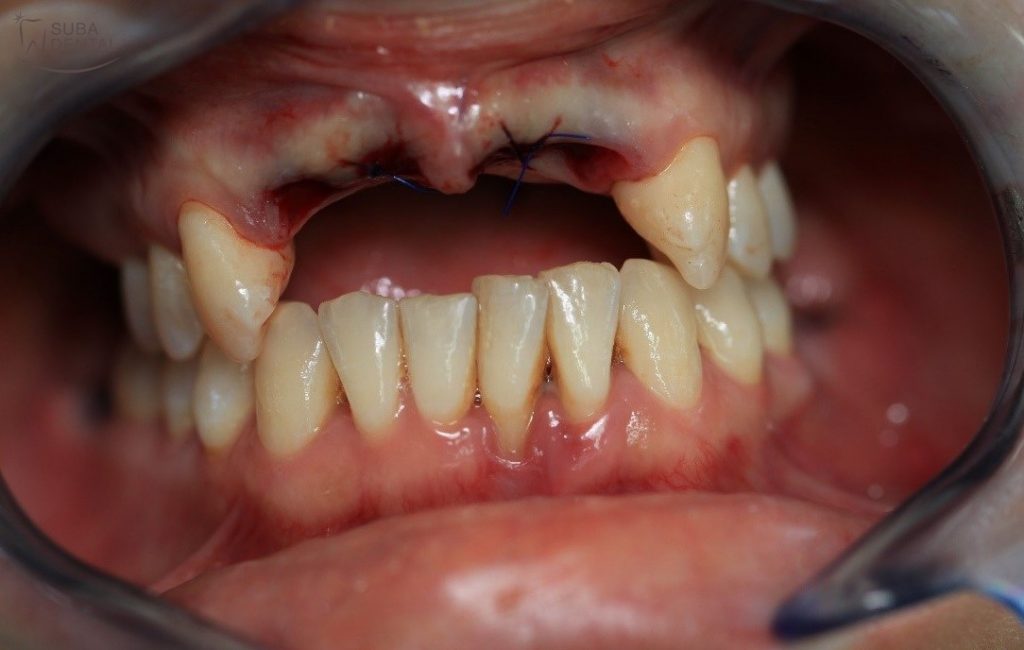

Fotó a fogak eltávolítása előttről

Fotó a fogak eltávolítása után. A sebet néhány varrattal zártuk a szebb és gyorsabb gyógyulás érdekében